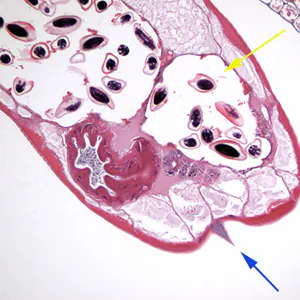

Gravid adult female Enterobius vermicularis deposit eggs on perianal folds

. Infection occurs via self-inoculation (transferring eggs to the mouth with hands that have scratched the perianal area) or through exposure to eggs in the environment (e.g. contaminated surfaces, clothes, bed linens, etc.)

. Following ingestion of infective eggs, the larvae hatch in the small intestine

and the adults establish themselves in the colon, usually in the cecum

. The time interval from ingestion of infective eggs to oviposition by the adult females is about one month. At full maturity adult females measure 8 to 13 mm, and adult males 2 to 5 mm; the adult life span is about two months. Gravid females migrate nocturnally outside the anus and oviposit while crawling on the skin of the perianal area

. The larvae contained inside the eggs develop (the eggs become infective) in 4 to 6 hours under optimal conditions

.

Rarely, eggs may become airborne and be inhaled and swallowed. Retroinfection, or the migration of newly hatched larvae from the anal skin back into the rectum, may occur but the frequency with which this happens is unknown.